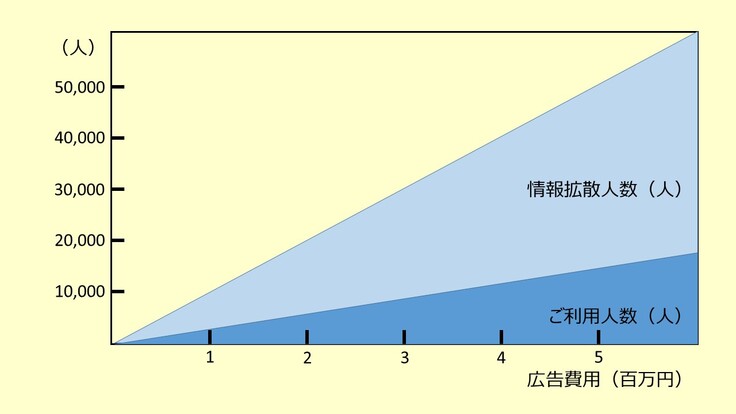

SNSでの広告単価は1クリックにつき3円程度必要です。その中で実際に使っていただける方の割合は数%程度と言われています。一方、検索サイトにおける広告単価は、検索に用いる用語が医学の専門用語であるために1クリックあたり100-200円と高価です。しかし検索サイトの場合は画像診断について検索された医療従事者のみに広告が表示されますので、実際に使っていただける方の割合はSNSよりも高く、10%以上期待できると考えています。

これらの予測から、全国の画像診断が必要な約30万名の医療従事者に対してどの程度の費用をかければ実際に何人くらいに情報が拡散し、何人くらいが使っていただけるかが予測できます(下図)。

このような費用対効果を考え、まずは検索サイトを中心とした広告宣伝活動を行いたく、50万円を目標金額に設定しました。その内訳は以下の通りです。

広報費:約 43万円(Google/Yahoo広告やSNSでの広告など)

手数料:約 7万円 (12%+税)